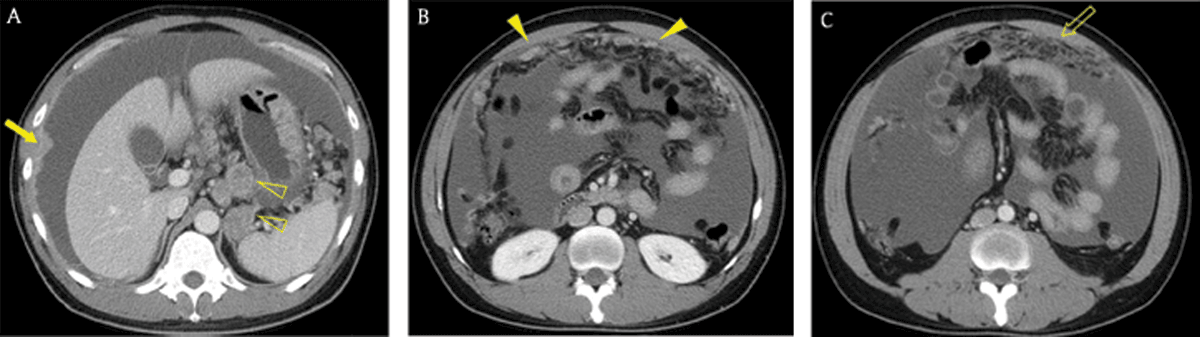

Figure 1

A 40-year-old man with advanced gastric cancer and peritoneal carcinomatosis. Axial portal venous phase CT images revealed multifocal discrete nodules (arrowheads) in the peritoneal cavity, peritoneal enhancement and thickening (arrow), ascites, and omental haziness (open arrow). Note the metastatic lymphadenopathy around the stomach (open arrowheads).